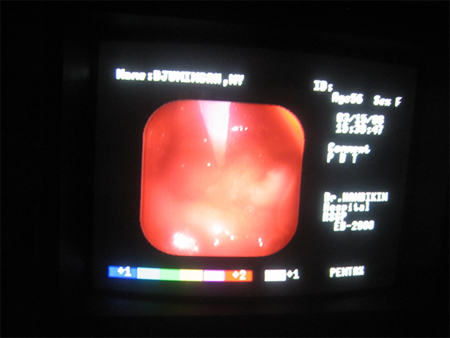

手术当中的胃镜截图